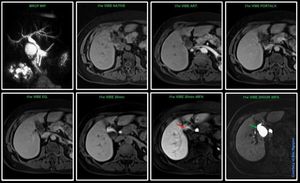

MR Abdominal Imaging – Primovist/Eovist @ Siemens 1.5T Avanto In this case Primovist was used to answer the clinical question regarding if this cyst communicates with the biliary system. The outcome of the exam shows that this cyst does communicate with the biliary system. Already after 20min post contrast (red arrow) you can see there is contrast in the cyst. Our rad wanted 2hour images since the patient had some other appointments in the house, so she just came back for one more scan. After approx. 2hour you can clearly see it does communicate (green arrow). Remember, the time window of the hepatobiliary phase with Primovist is approx. from 20min – 2hour.#Siemens_MRI #siemens #mri #primovist